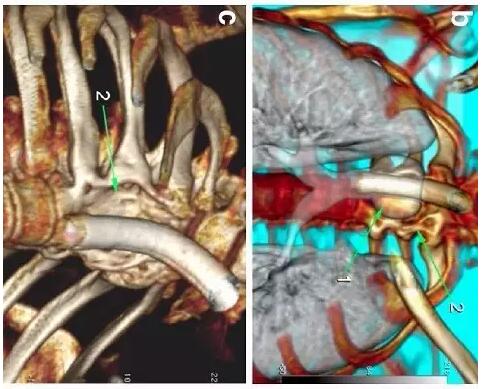

胸部CT顯示氣切套管氣囊周圍氣管擴張,胸1-4椎體前部受到侵蝕(下圖a-c)���。

下圖箭頭1為氣切套管氣囊緊貼T1-4椎體水平��,造成椎體前部受到侵蝕(箭頭2):